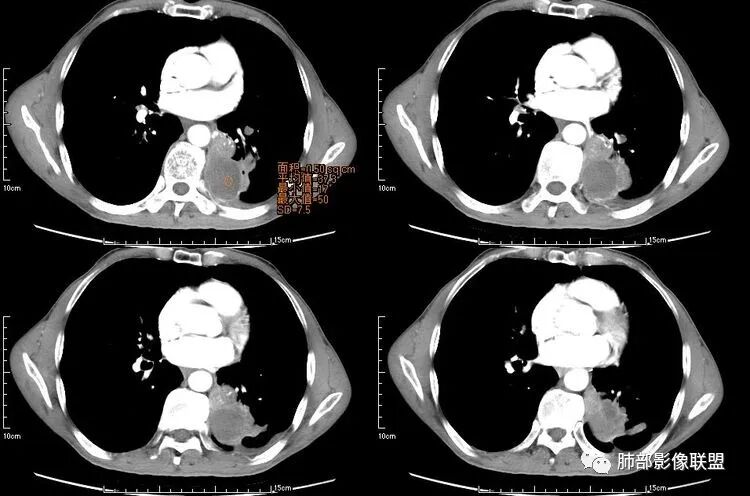

患者老年男性,咳嗽、咳痰、痰中带血伴胸闷2月余。长期大量吸烟史。查肝肾功能、血糖、血脂、心肌酶、电解质、血沉、C反应蛋白、抗“O”、类风湿因子、抗核抗体谱无明显异常。肿瘤标志物提示NSE、CYFRA21-1稍升高。胸部CT:肺气肿背景,左肺下叶后基底段不规则肿块影,见支气管截断,内见大片状低密度区及部分血管影,增强轻度强化,远端空洞形成。双肺多发不规则实性结节影、见毛刺、胸膜牵拉及血管集束,结节内见空洞形成,部分可见血管影,多位于胸膜下。双肺见多发肺大泡。综合考虑左下肺恶性病变并双肺转移。鳞癌或淋巴瘤可能。鉴别血管炎性病变及真菌感染。

左肺下叶团块病灶,有明显张力,增强后病灶内部有可疑延迟强化,看不清楚病灶与支气管的关系,应该支气管受压阻塞了,双肺多发胸膜下小结节,病灶小结节病灶有平行胸膜生长的表现,部分小结节厚壁,部分薄壁,,还有一部分有内容物,这需要两元论,左肺下叶肺癌(腺癌)伴转移,同时合并真菌感染。

液化,而不像坏死,是有强化的;这个里面似有液平。说明里面有分泌粘液?

无发热,其他慢性细菌先不考虑,有的低毒的,但是结节形态还是比较不规则的,分布也是比较随机,更像原发病灶。真菌方面,结节没有融合,坏死也是液化坏死,不符合隐球菌,曲霉不符合IPA,慢性吸入的也少见。结核没有树丫,不考虑。鉴别主要是GPA,和肺癌。GPA不支持点是皮肤,肾脏没有累及,ANCA不支持。。。肺癌主要是腺癌和鳞癌转移。比较支持的是淋巴结肿大,和左下肺的主病灶,支气管堵塞和异常强化。还有分叶,局部膨隆。可以建议支气管镜检测。

本病例左肺下叶肿块,有深分叶、毛刺、胸膜牵拉凹陷、支气管截断及纵隔内淋巴结肿大等征象,都均支持病灶为恶性,如腺癌,而且叶间裂的多发结节也提示是腺癌来源可能大;双肺多发结节、肿块,大部分病灶有分叶、毛刺及胸膜凹陷的恶性征象,与原发肿瘤本身的性质有关,所以应该与左肺下叶肿块同源,而且双肺多发病灶内空洞也具有多样性;